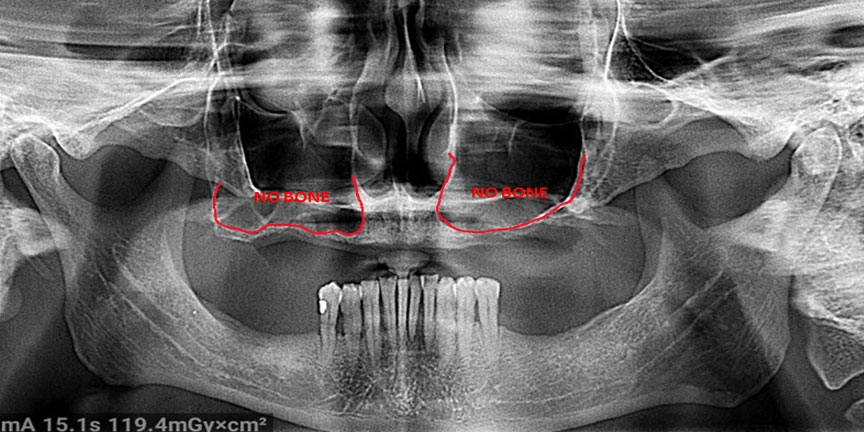

Difficult Cases

We treat patients when other providers cannot manage. CLICK HERE

Severe Bone Loss